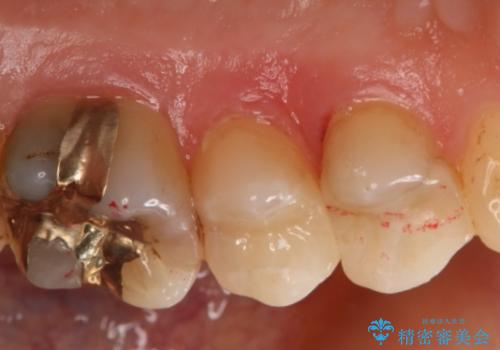

- 左上奥歯の銀歯のやり変えを希望された患者様です。

白くしたいとの事だったので形態・切削量を考慮し、セラミックインレーでの治療を計画しました。

保険材料と比較し、セラミックは劣化しない材料なので二次的な虫歯を防ぐことが出来ます。